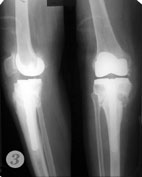

Пример №5 Эндопротезирование коленного сустава

1,2 до операции

3. после операции по эндопротезированию коленного сустава